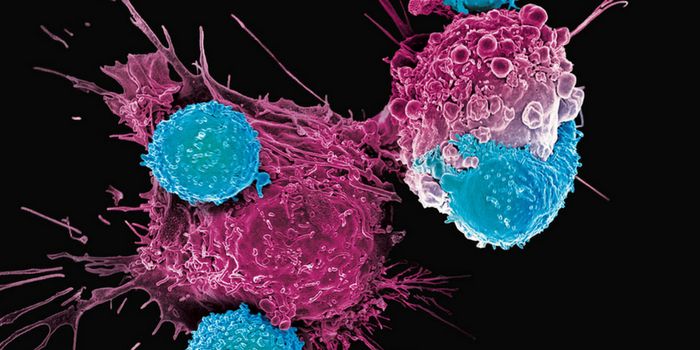

JUL 25, 2022CancerAdvancements in immunotherapy have proven instrumental in reshaping the face of cancer research in recent years. W ...

FEB 15, 2023InfographicsOver the past decade, advances in immune-based therapeutic approaches have drastically expanded cancer treatment options ...

DEC 14, 2018CancerChimeric antigen receptor T cells (CAR-T cells) have emerged as a useful tool for cancer treatments in a small number of ...